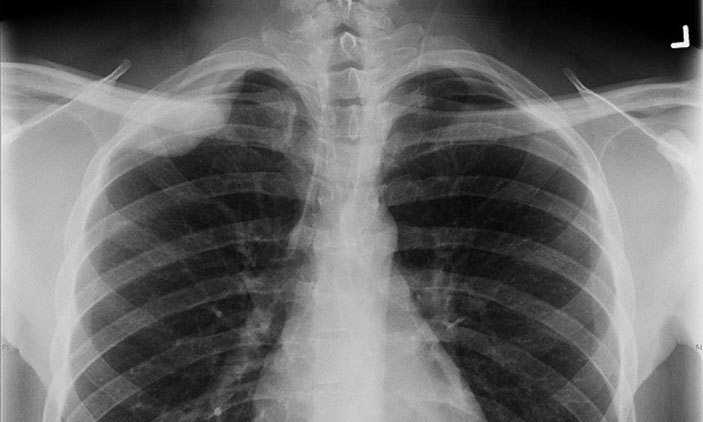

77 per cent X-Ray facilities in Karnataka unlicensed; Directorate of Radiation safety to be set up

BENGALURU: There are at least 20,000 X-ray centres in Karnataka (both government and private health facilities), but only 4,500 have licences from Atomic Energy Regulation Board (AERB), Mumbai. On Saturday, Karnataka signed an MoU with AERB to set up a Directorate of Radiation Safety. Through registration, site approval and licensing in such facilities, AERB’s mandate is to ensure that the use of ionising radiation and nuclear energy does not cause undue risk to the health of people and the environment. A Supreme Court judgment mandated every state to establish a directorate of radiation safety (DRS) to support the AERB in governing radiation safety. Dr Swatantra Banakar, state nodal officer, radiation safety, said, “In our state, we have no licensing authority for imaging centres of any kind. The only licensing authority is in Mumbai, which is the AERB. Only 4,500 are registered with them. The remaining 15,500 are unlicensed, which is 77 per cent. So we have signed an MoU with AERB to have a radiation safety division in Karnataka. The office will be operational in one-and-a-half months.” Once the division is operational, the radiation safety officers will check whether nursing homes, clinics and diagnostic centres have licences and whether they are following AERB norms. Henceforth, whenever new centres are set up, they will be required to take permission from the AERB and DRS. “For a CT scan, the walls of the MRI room have to be at least nine inches thick. The personnel have to wear aprons and there should be boards outside alerting pregnant women. There should also be boards informing the patients on the amount of radiation in the room. The windows should be closed. These are the norms to be followed from the AERB,” he added. Atomic Energy (Radiation Protection) Rules, 2004, provides the legal framework for the safe handling of radiation generating equipment. As per rule 3, it is mandatory for all users of X-ray equipment to obtain requisite licence from AERB. Source: Indian Express